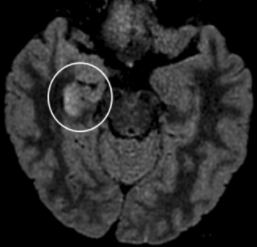

In the circled area of the chart below, you can actually see the inflammation taking place.

White tissue shows inflammation in the temporal lobe

"A brain MRI showed hyperintensity along the wall of right lateral ventricle and hyperintense signal changes in the right mesial temporal lobe and hippocampus, suggesting the possibility of SARS-CoV-2 meningitis. This case warns the physicians of patients who have CNS symptoms."